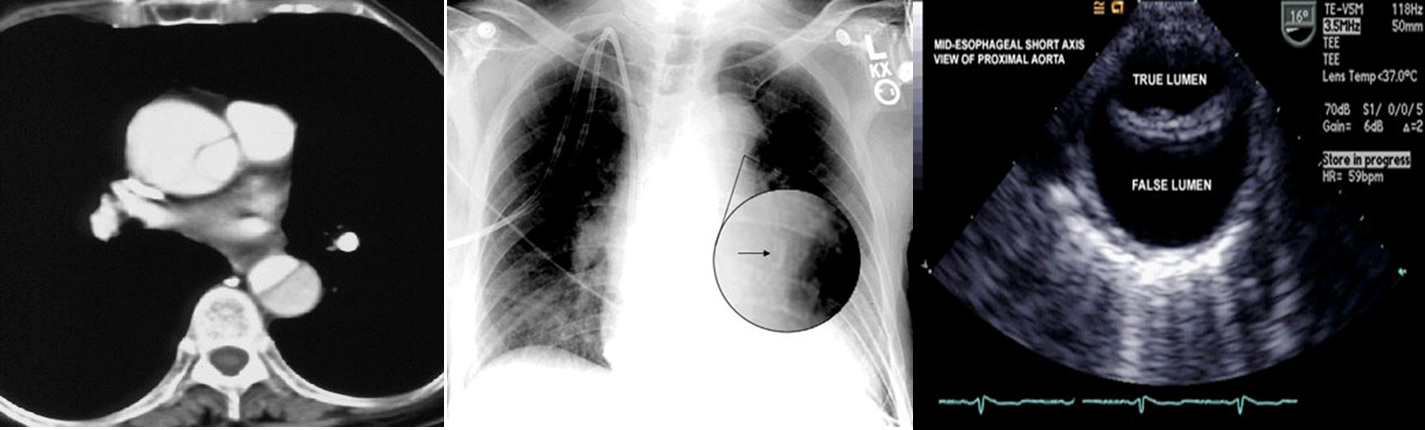

What is your diagnosis Dissecting aortic Aneurysm

This is a case of large pericardial effusion (tachycardia, a low voltage recording, and the electrical alternans.